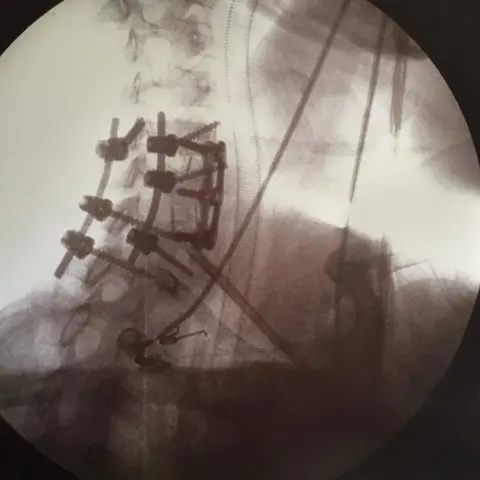

The former coffee shop worker was injured on 1 December and has since undergone 10 hours of surgery.